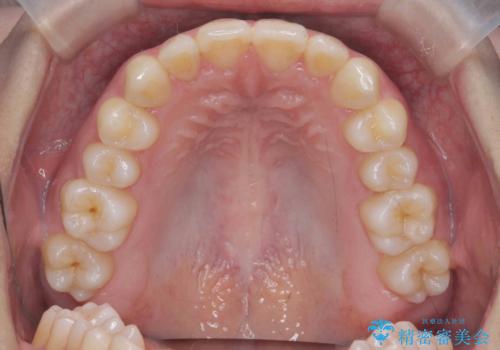

マウスピース矯正で前歯のガタつきを改善

- 上下の前歯のガタつきの改善を求めて、矯正治療を希望され来院されました。

矯正検査の結果、マウスピース矯正システム インビザラインの適応であることからワイヤーを用いず矯正治療を進めることとしました。

1日20時間以上の使用時間をきっちりと守っていただけたため、良好な治療結果、歯並びを手に入れることができました。